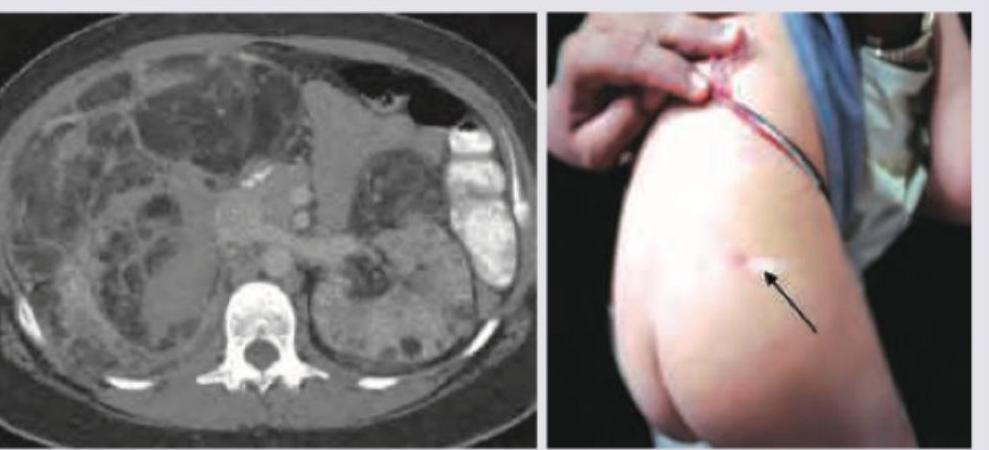

Question 13: A 2-year-old mentally retarded child with the marked skin lesion presents with left side flank pain. CT scan of abdomen shows -50 to -60 HU densities of the lesions in kidney and liver. The most probable diagnosis is?

- A. Familial Angiolipomatosis

- B. ADPKD

- C. V.H.L

- D. Tuberous sclerosis (Correct Answer)

Explanation: ***Tuberous sclerosis*** - The combination of **mental retardation**, **skin lesions** (ash-leaf spots are shown in the image), and **renal/hepatic lesions** with characteristic negative HU densities (-50 to -60 HU, consistent with fat in angiomyolipomas) is highly suggestive of Tuberous Sclerosis Complex. - Tuberous sclerosis involves benign tumors (hamartomas) in multiple organs, including the **brain**, **skin**, **kidneys** (angiomyolipomas), and **liver** (hepatic angiomyolipomas), which explains the diverse clinical presentation. *Familial Angiolipomatosis* - While it involves **angiomyolipomas**, it typically does not present with the widespread neurological abnormalities like **mental retardation** or characteristic skin lesions seen in Tuberous Sclerosis. - This condition is often limited to the presence of multiple bilateral renal angiomyolipomas. *ADPKD* - **Autosomal dominant polycystic kidney disease (ADPKD)** primarily involves numerous **renal cysts** with positive or near-zero Hounsfield units (HU), and sometimes hepatic cysts, but does not present with **mental retardation** or **fat-containing lesions** (negative HU) in the kidneys or liver. - The cystic lesions in ADPKD typically have HU values similar to water (0-20 HU). *V.H.L* - **Von Hippel-Lindau disease (VHL)** is characterized by **hemangioblastomas** of the CNS and retina, **renal cell carcinoma**, **pheochromocytomas**, and **pancreatic cysts/tumors**. - VHL does not typically cause the **skin lesions** (ash-leaf spots) or **mental retardation** as described, nor are the kidney lesions characterized by negative HU on CT.